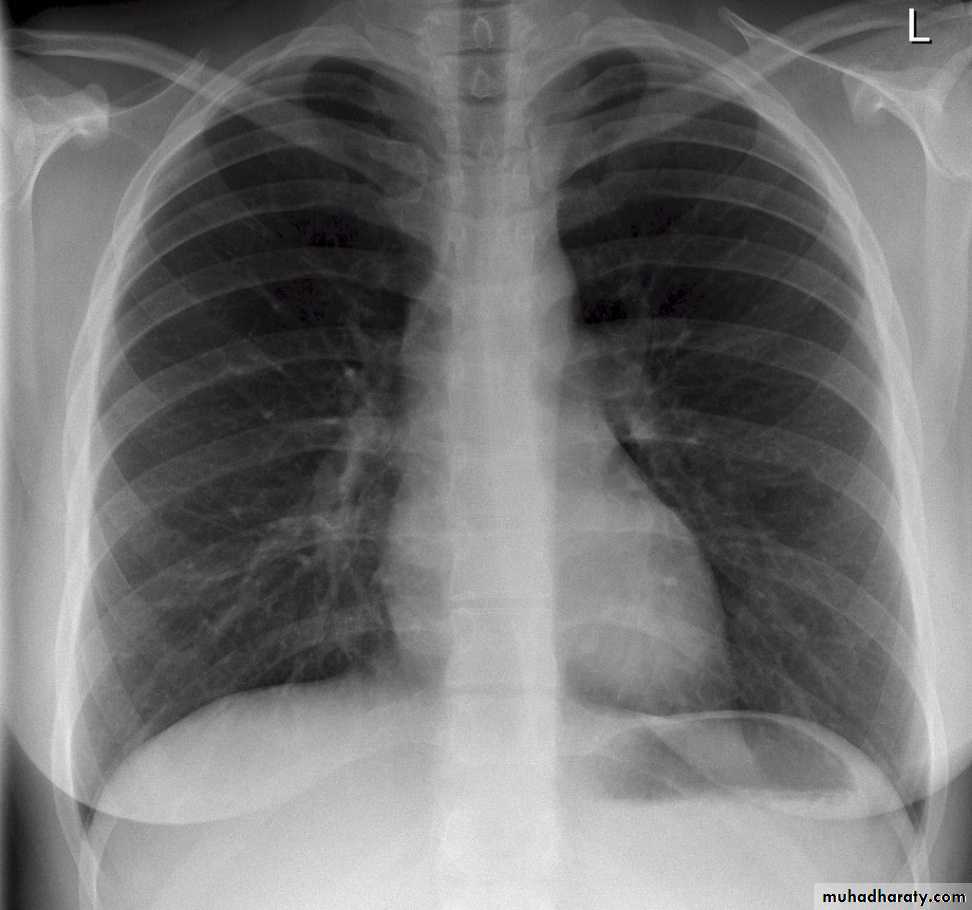

• Pleural effusion : collection of fluid within the pleural space. This can be further divided into Transudate , exudate, according to protein content .Other type of fluid collection within pleural space are

• Chest x-rays are the most commonly used examination to assess for presence of a pleural effusion, however it should be noted that on a routine erect frontal chest x-ray as much as 200-500 ml of fluid is

• required before it becomes evident .

blunting of the costophrenic angle

blunting of the cardiophrenic angle

fluid within the horizontal or oblique fissures

eventually a meniscus will be seen, on frontal films seen laterally and gently sloping medially

with large volume effusions, mediastinal shift occurs away from the effusion

Pleura effusion signs

Obliteration of costo-pherinic anglesMeniscus sign

Lenticular sign

A subpulmonic effusion

(infrapulmonary effusion) accumulation of fluids between the lung & visceral pleura ..The following features are helpful :elevation of the hemidiaphragm ..right: peak of the hemidiaphragm is shifted laterally

left: increased distance between lower lobe air and gastric air bubble